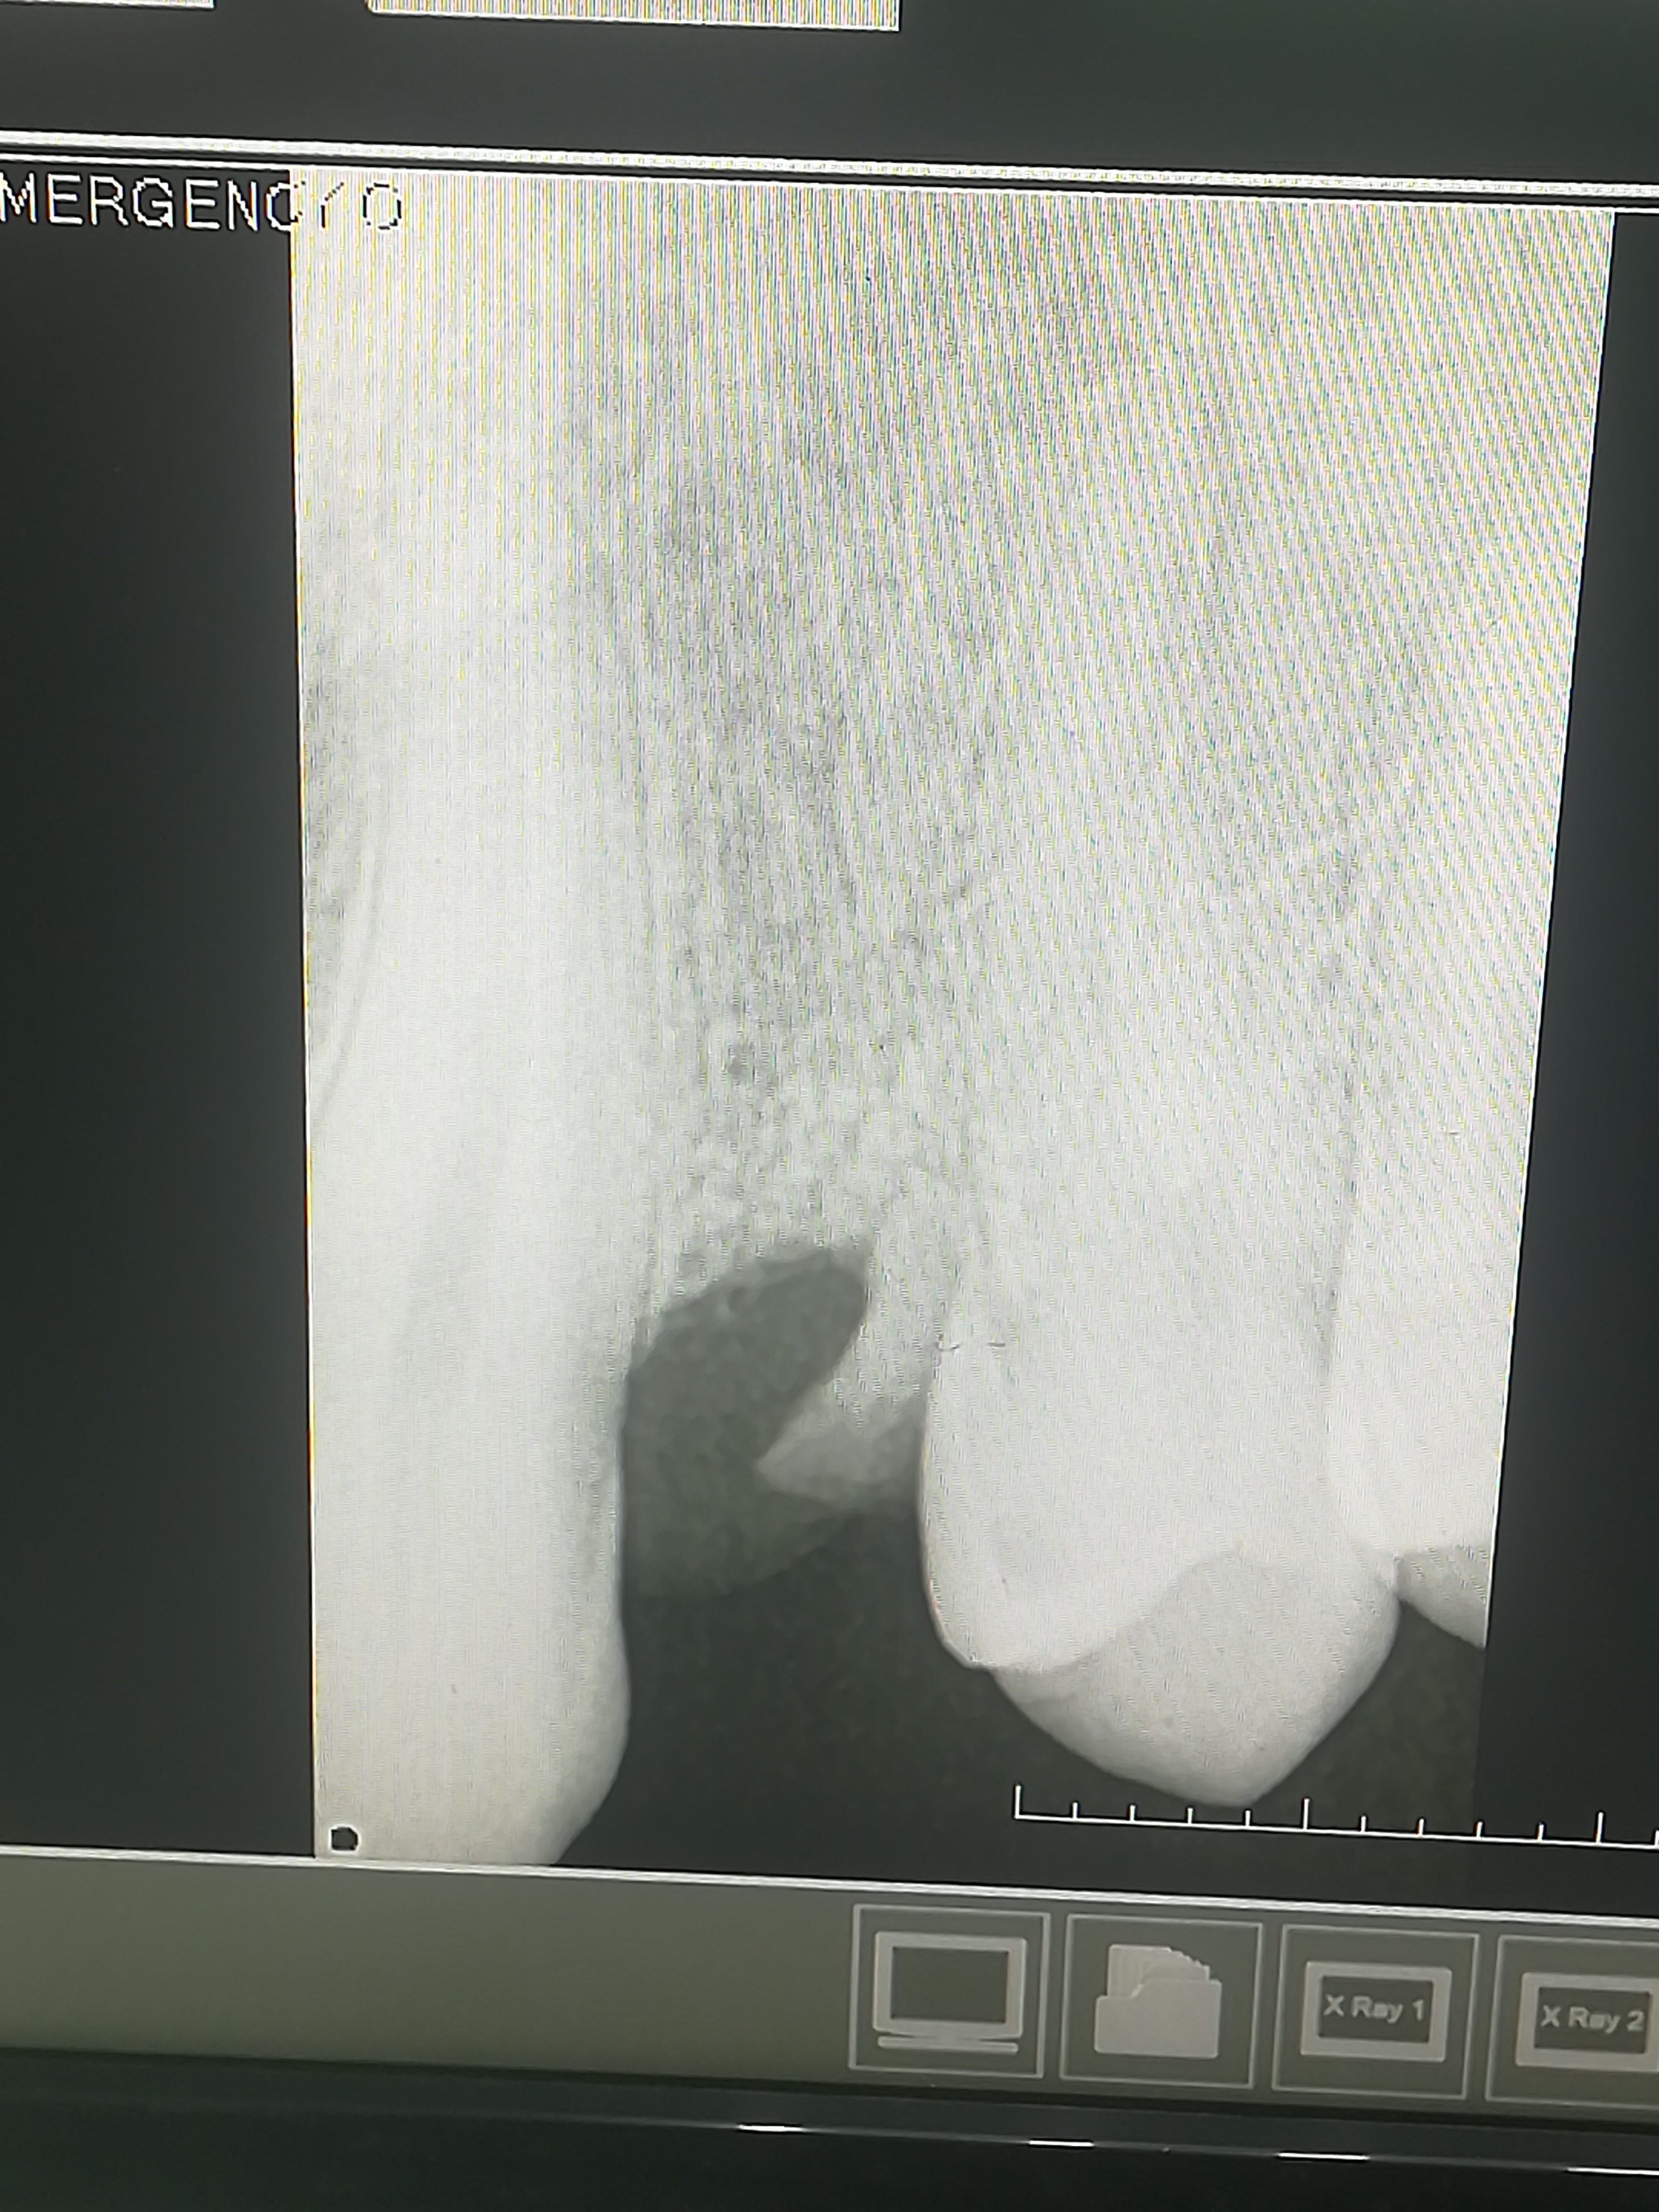

2323.jpg 238Кб, 1412x2047

1412x2047

Аноны, добрый вечер.

Посоветуйте пасту зубную после пломбирования и чистки от камня передних зубов.

Спасибо.

Аноним 06/08/25 Срд 05:38:29 1634925 25

Ска, весь рот в гное, будто бы стоматит, сходил к зубным феям - сказали все збс с корнями зубов и ни одного намёка на кариес где-либо, хотя начиналось всё будто бы флюс и самый пиздец около одного зуба, прописали онли антибиотики, но самое очко , что болезненность ещё и в области мягких тканей подбородка, который и отдает в этот самый пиздец при надавливании - даже будто бы второй подбородок чуть-чуть присутствует, температура и общая слабость, есть риск флегмоны? пиздец за шо(

Аноним 06/08/25 Срд 10:08:53 1634947 26

Как профиль лица меняется после удаления восьмерок? В инете нашел только фотки до/после у женщин, и вроде как челюга уменьшается. У мужиков так же? После удаления не получится больше моггать челюхой омежек?

Аноним 07/08/25 Чтв 13:36:06 1635134 27

>>1634947

>Как профиль лица меняется после удаления восьмерок

Удаляли две, одну сверху другую снизу. Никаких изменений.

Но если у тебя они кривые и растут вбок например то конечно станет лучше

>>1633720

>6 мес. после чистки и пломбы перед коронкой подождат

Ну какие нахуй 6 месяцев? Анон я за 5 дней уже умираю нахуй, он его не долелал чтоли что я чувствую все и жевать им не могу. Буквально еду пью уже вторую неделю

Ну ебало моё представляешь, пока с одной стороны делают жуешь другой стороной, и тут ещё одна дырка на зубе. Ну не пиздец а? С обеих сторон по 1. Началась та же ипопея кто мне сделает сейчас а не через месяц. Сделали, 3 часа сидел, и успели временную пломбу поставить которая на следующий день вылетела

Вот по итогу, рот болит, зубы болят, минус 20 тыс, пью еду.